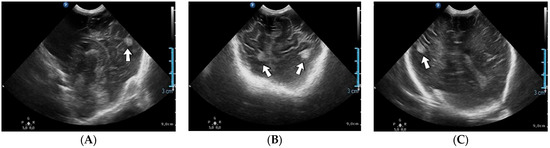

4.17. Case No. 17—Postnatal Cerebral Thromboembolism

A 13-day-old female neonate (33 weeks, 1.50 kg) presented with a suspicion of a left pulmonary sequestration, confirmed on an admission CT scan, and severe pulmonary hypertension. Two weeks after admission, the patient developed severe bradycardia. A head ultrasound after the event indicated various hyperechoic lesions in the left temporal and parietal lobes and right insular and parietal lobes (Figure 7). The laboratory findings from that time showed anemia and elevated, but decreasing c-reactive protein. A lumbar puncture was performed, with a normal result.

Figure 7.

Cerebral thromboembolism on brain ultrasound: parietal lobes (A–C).

Genetic testing confirmed inherited thrombophilia, with a positive MTHFR A1298C heterozygous gene mutation and Antithrombin deficiency. There was a positive maternal history of miscarriage before this pregnancy.